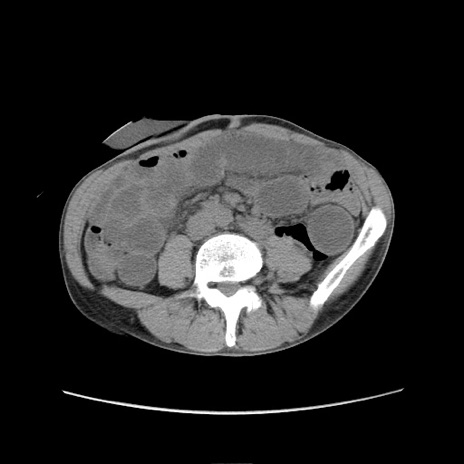

症例11(横断像)

【症例】 60歳代男性

【主訴】 下腹部痛

【現病歴】 本日夜中より下腹部痛の症状認め、受診。

【既往歴】 膀胱癌(膀胱全摘+尿管皮膚瘻術) 、胃癌術後

【身体所見】 BT 35.3℃、PR 58/min、BP 136/98mHg、腹部平坦、軟、腸蠕動音±、ストマ留置あり、左上腹部~正中部に圧痛あり、反跳痛なし。

【データ】WBC 5100、CRP0.01